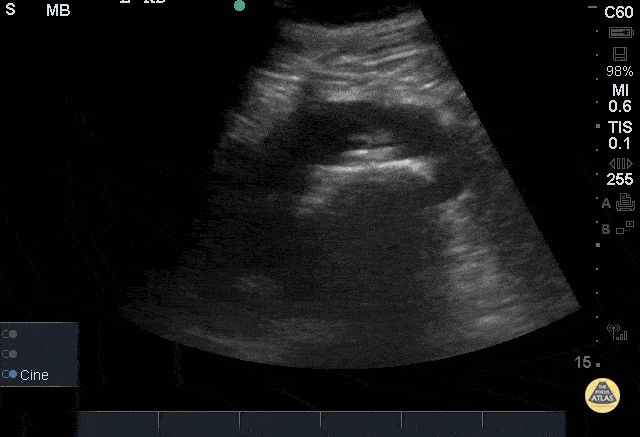

51yoM with history of staghorn calculi presenting with hematuria and left lower quadrant pain x 3 days. Ultrasound of left kidney in sagittal plane using a phased array 5-1MHz probe demonstrating a large hyperechoic structure in the renal pelvis with associated posterior acoustic shadowing consistent with staghorn calculi. Ultrasound serves as a low-cost, readily available method without radiation which can aid in the detection of renal or ureteral calculi. (Nicolau 2015)